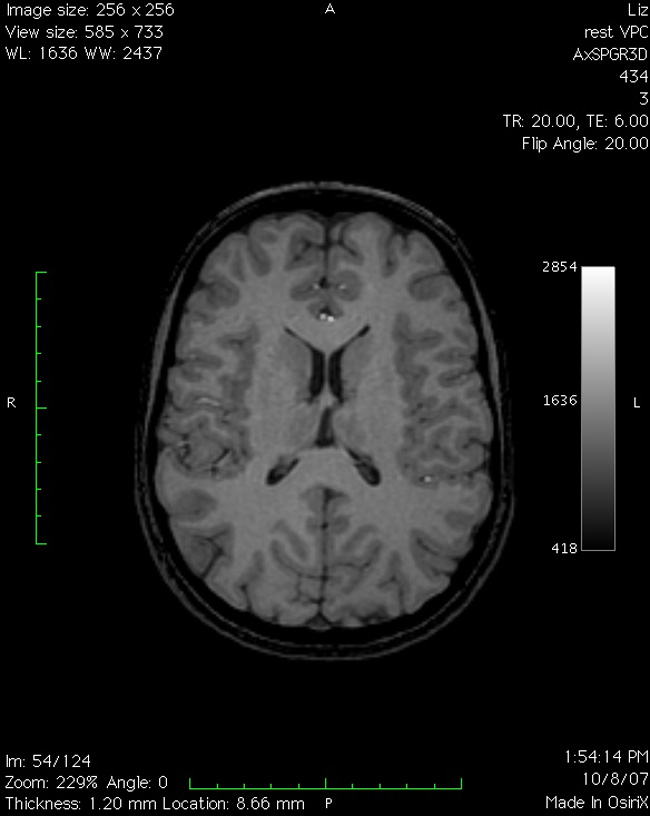

TERRENOS ESCANEADOS/fMRI on an Affordaplane surface

. Basement installation (entry from N.Hancock Street, Richmond, VA); initiated by a neuroimaging experiment. 2008.